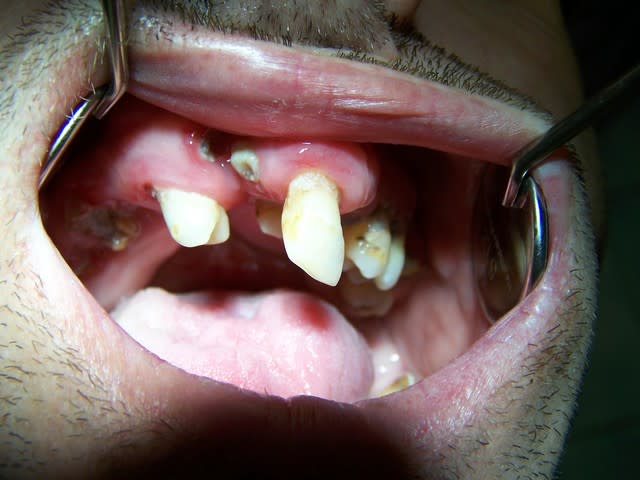

Photos en bouche (après autorisation du patient, quand même...):

Bdl2 asoeq1 - Eugenol

Bdl3 spkgaf - Eugenol